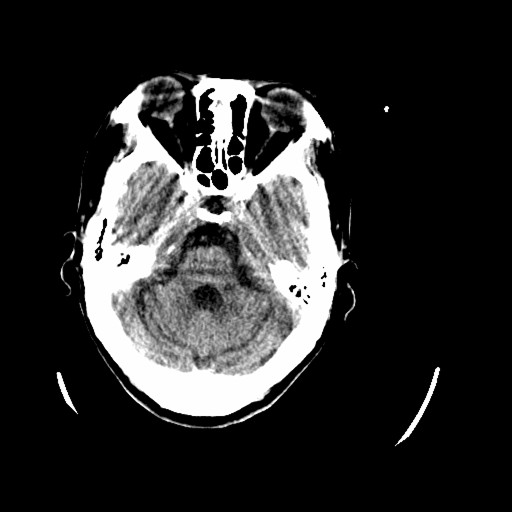

标题: CT16233:女,44岁,智障多年,现感头痛 [打印本页]

标题: CT16233:女,44岁,智障多年,现感头痛

小脑有啥病变?

橄榄桥小脑萎缩.左侧小脑脚腔梗.

橄榄桥小脑萎缩可能,建议mri进一步检查以进一步排查。

橄榄桥小脑萎缩